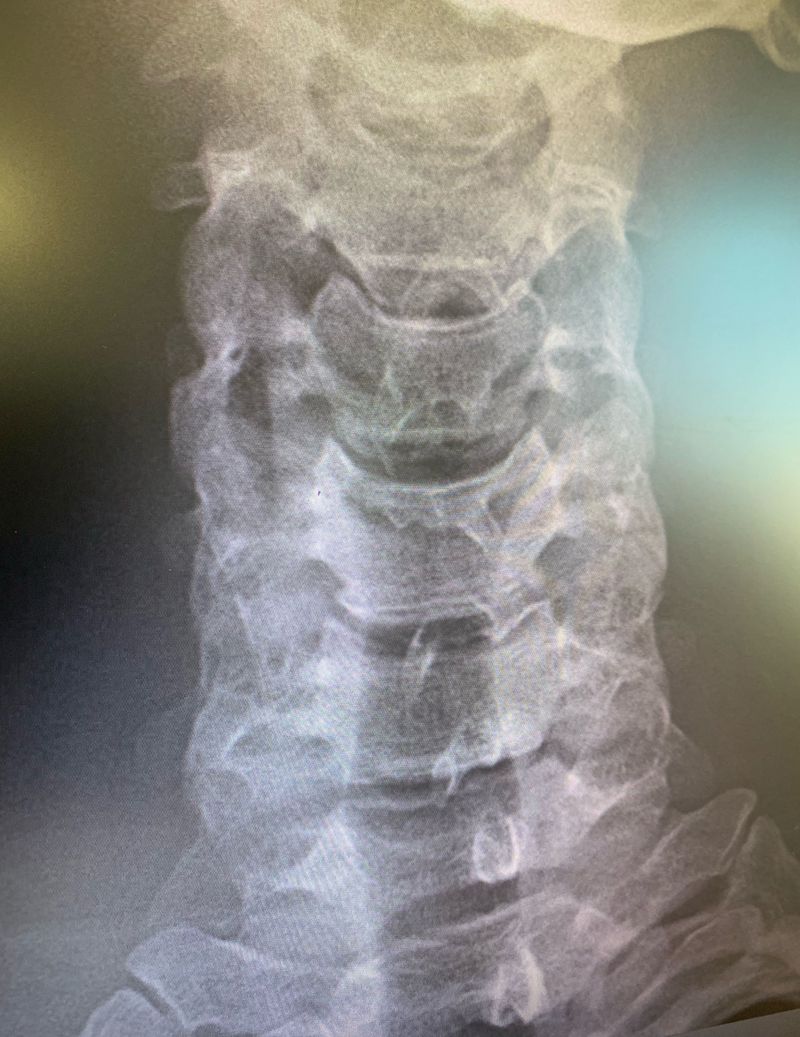

Something strange in these cervical?

What do you see! Comment below!

The transverse processes of vertebrae are really huge!!

Spinous processes are not in a single line

Scoliosis